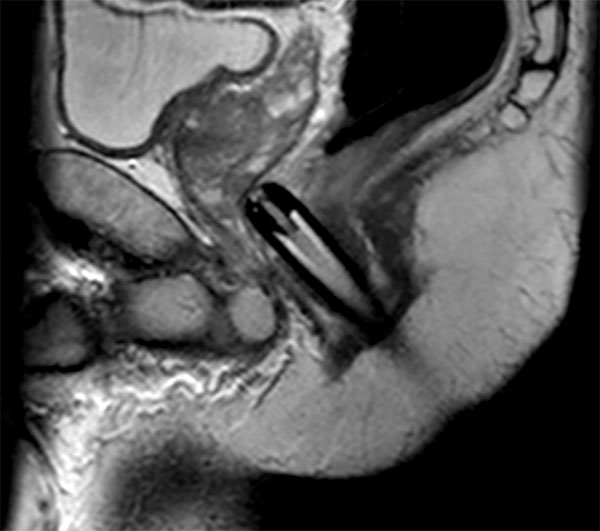

73 year old male with known prostate carcinoma. Size of 5mm, located in right posterior region. Patient is under active surveillance. Request for MR-guided prostate biopsy to re-evaluate.